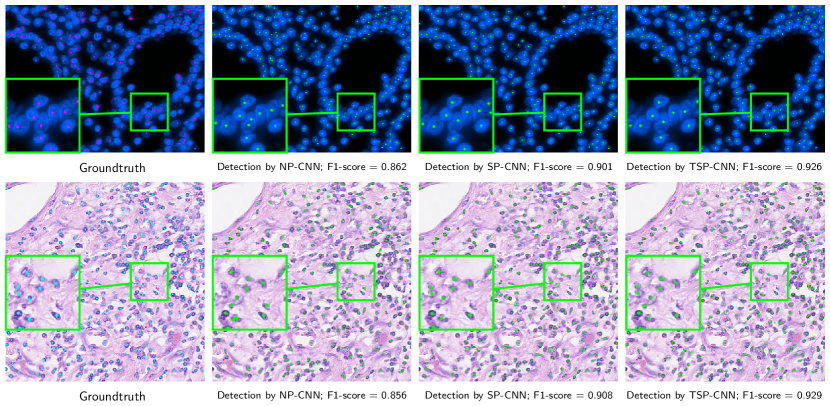

Figure 14 provides further insight into the merits of SP-CNN and TSP-CNN for two test images from each dataset. We compare TSP-CNN and SP-CNN with the top two methods from Table III and Table IV, i.e. SC-CNN [5] and SR-CNN[16]. Two parts of each image in Fig. 14 are magnified for convenience. While ‘green’ zoomed areas show the missed detection by SC-CNN and SR-CNN, ‘magenta’ ones show the wrong detection (FP) of nuclei by those methods. Thanks to learning guided by pertinent prior information, SP-CNN and TSP-CNN avoid false positives, which are still detected as nuclei by competing state of the art methods.

In the same spirit, we present results for TSP-CNN, SP-CNN, and NP-CNN in Fig. 15. In this figure, we can observe that shape priors indeed help to improve the detection results and tunable shapes improves the performance of SP-CNN even further. In Fig. 15, note that the detections made by NP-CNN, SP-CNN and TSP-CNN nearly capture all the nuclei centers for the example image from the PSU dataset. Yet, SP-CNN and TSP-CNN perform better because guided by shape priors, false positives are significantly reduced. For the UW dataset, benefits of SP/TSP-CNN are evident over NP-CNN for which two missed detections and one false positive can be seen in the zoomed part of the image.